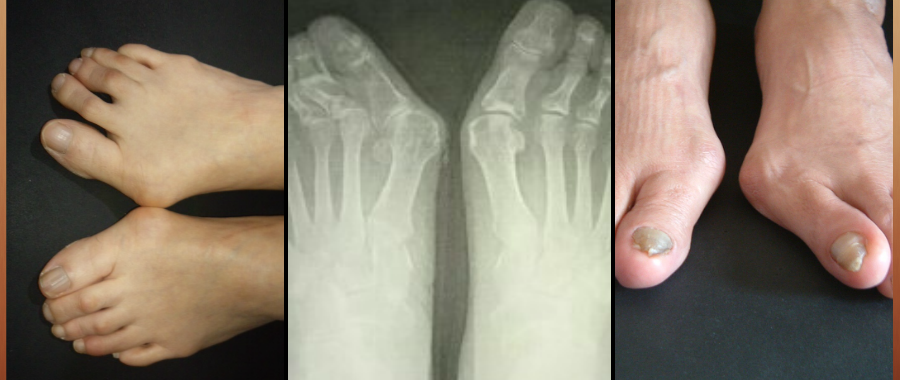

外反母趾、モートン病、ハンマートゥ、巻き爪、魚の目など靴が原因で足を悪くしてしまったのか、

市販の靴でこのような変形、症状は作られますが、私どもの靴づくりは変形した足、痛みなどに対応し、靴型から作られます。

外反母趾、リウマチ、膠原病、など靴が足に合わない事で足の変形だけでなく、